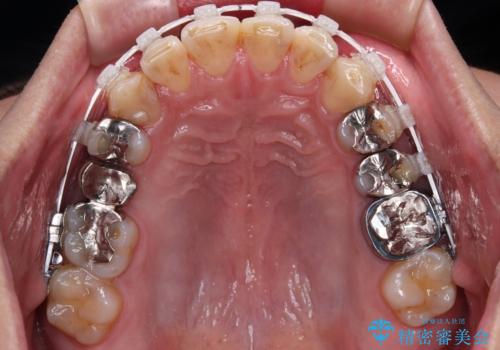

抜歯が必要な歯は事前に抜歯をし、その後ワイヤー装置にて歯列矯正を行い、途中でインプラントを埋入し、オールセラミッククラウンにて補綴治療を行うこととしました。

矯正治療にやや時間がかかりましたが、歯列はきれいに整い、気になっていたむし歯や銀歯は自然な色合いに仕上がりました。